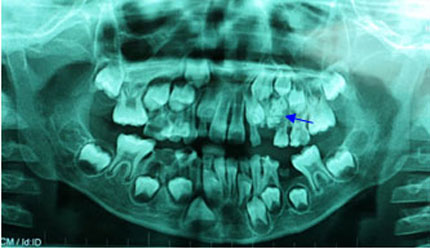

Ảnh chụp X quang hàm răng của bé trai 7 tuổi. |

Bé được tiến hành chụp phim X-quang để khảo sát. Trên phim toàn cảnh, bác sĩ phát hiện có một khối cản quang không đồng nhất, giới hạn tương đối rõ, ở vùng xương hàm trên bên trái, và nằm cạnh khối u là chiếc răng nanh sữa, đó chính là chiếc răng mà bác sỹ đang quan tâm tìm hiểu.Khối cản quang đó được chẩn đoán là u răng, một loại u răng sinh lành tính thường gặp ở vùng xương hàm.